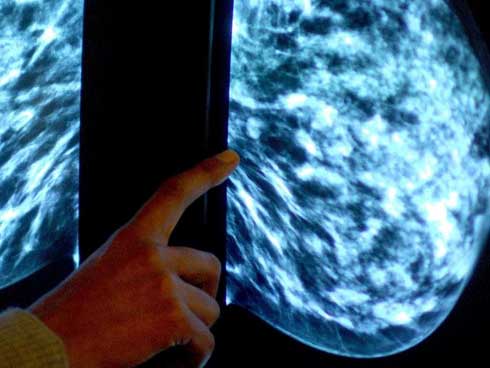

Bỏ được thói quen ăn khuya, nguy cơ ung thư vú hoặc tuyến tiền liệt của bạn có thể giảm đến 20% - ảnh minh họa từ internet